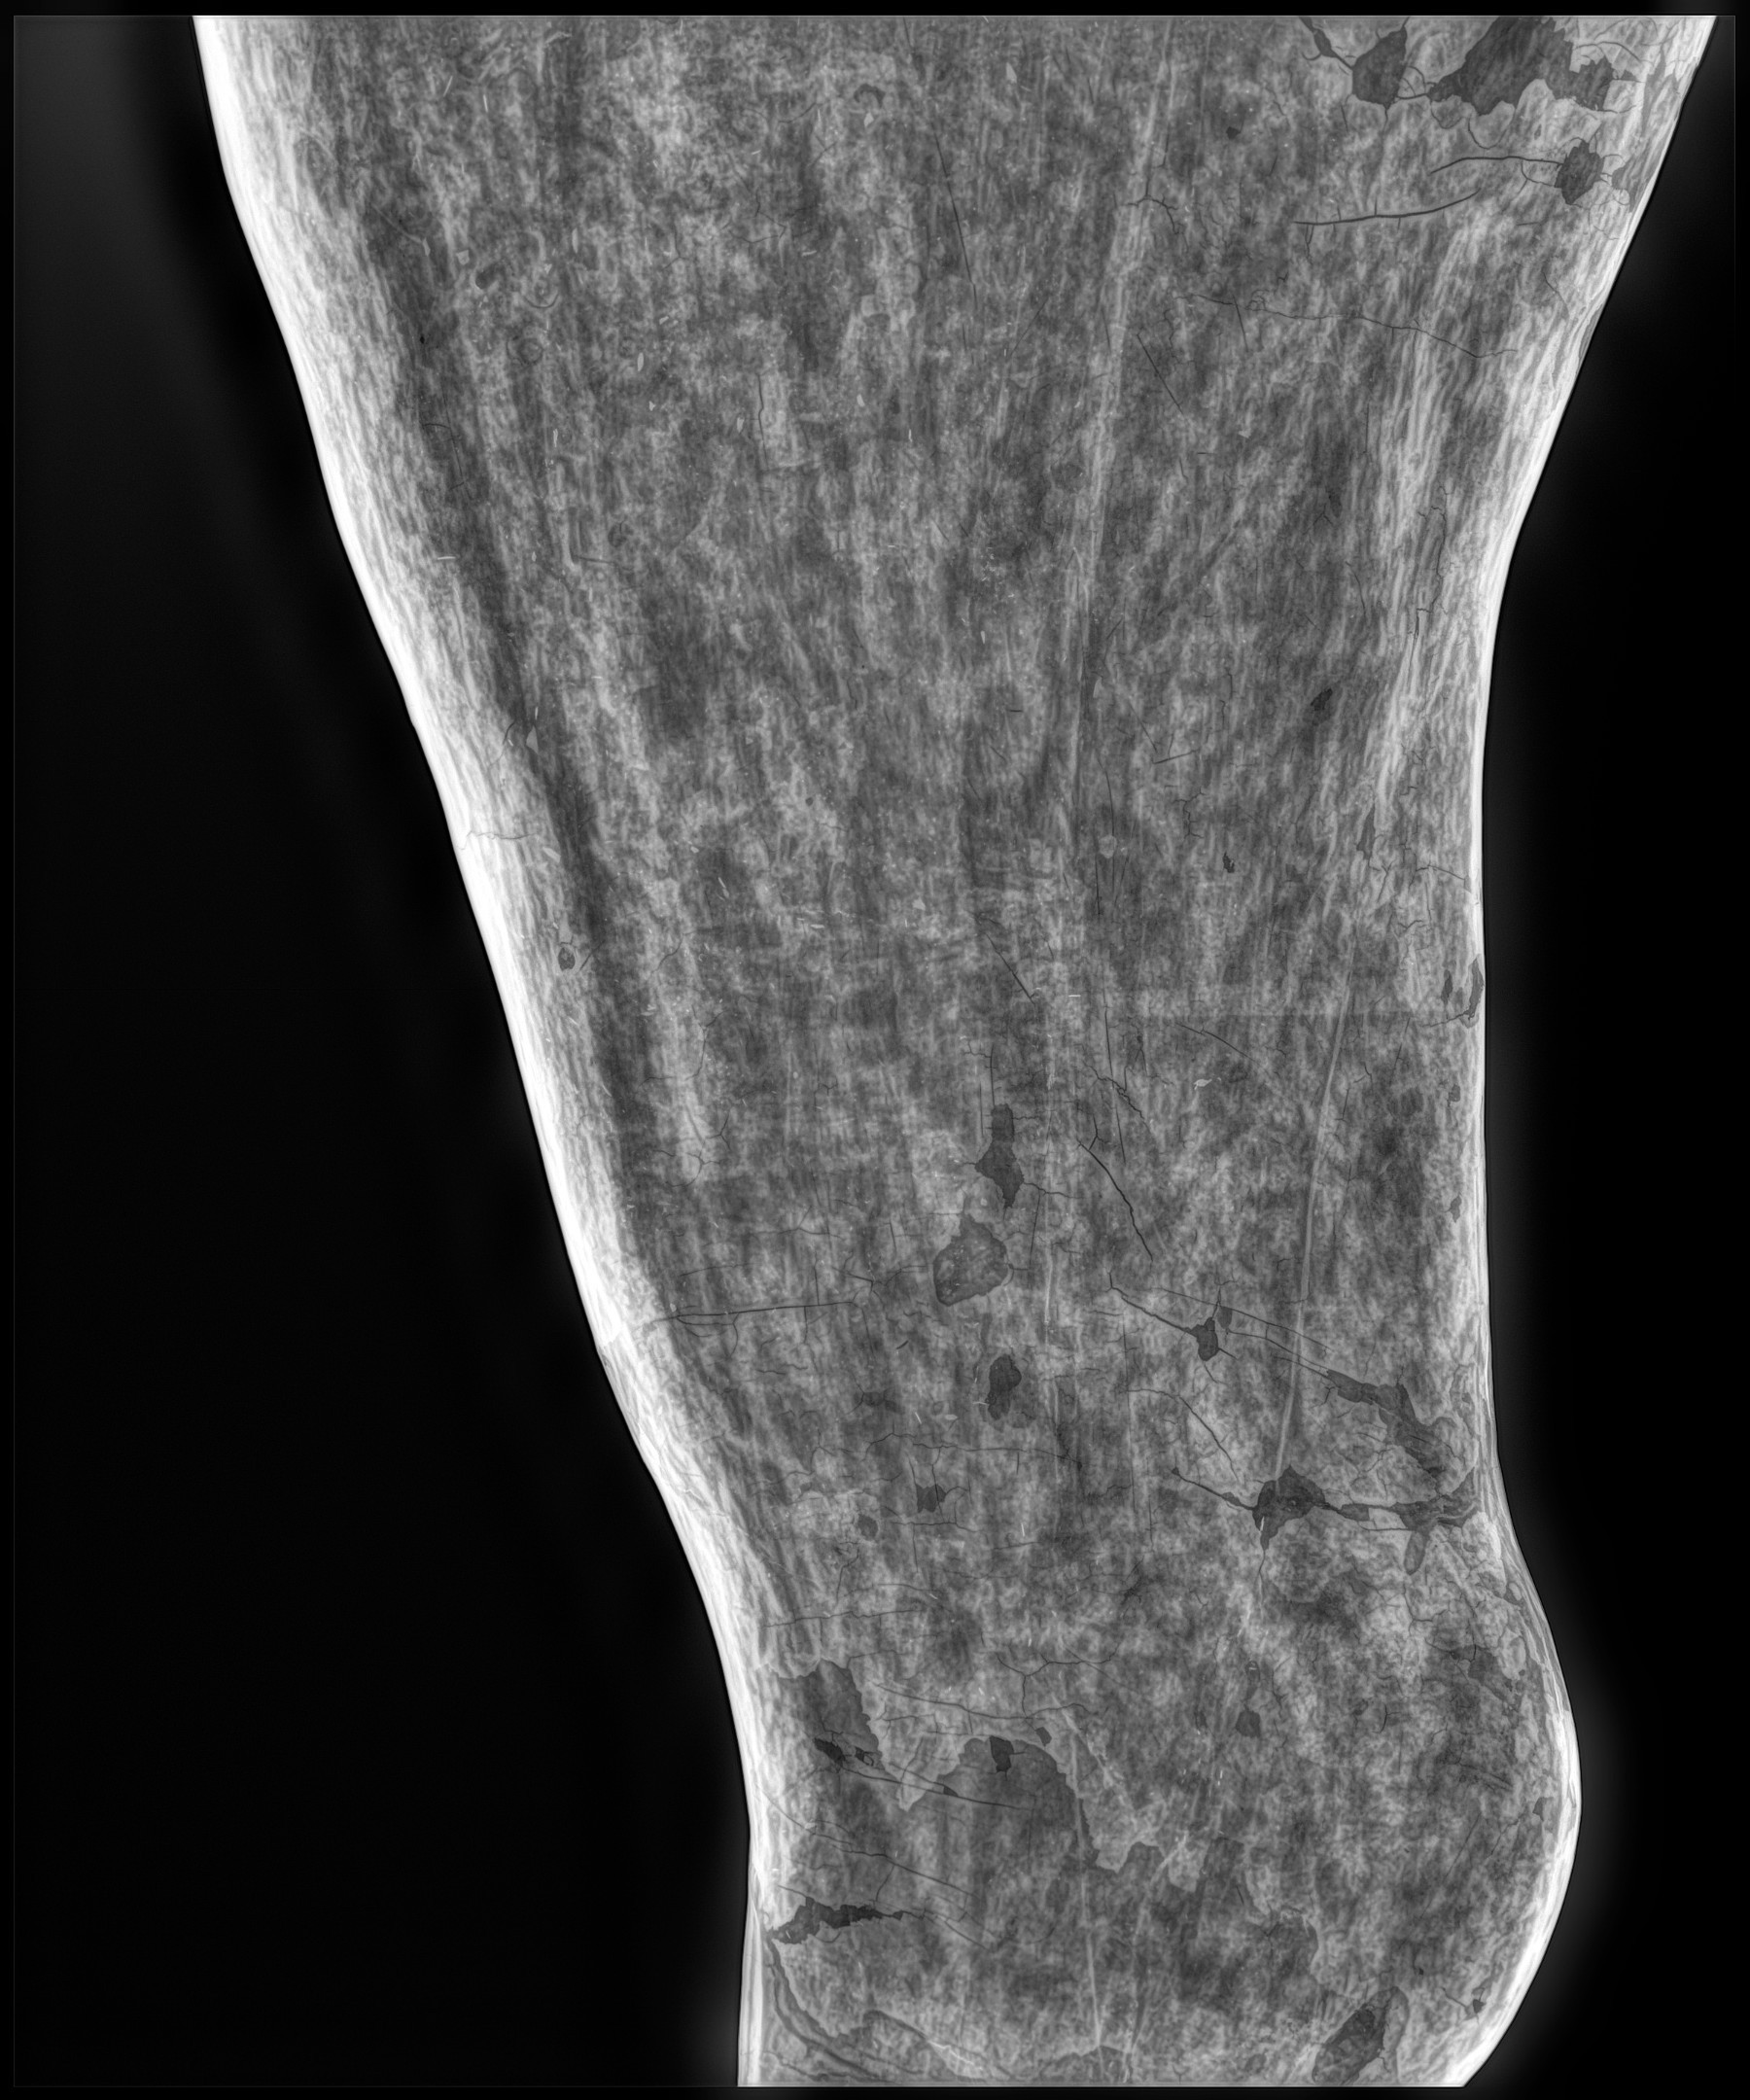

Radiología Digital como Herramienta Complementaria en el Dictamen de Bienes Muebles